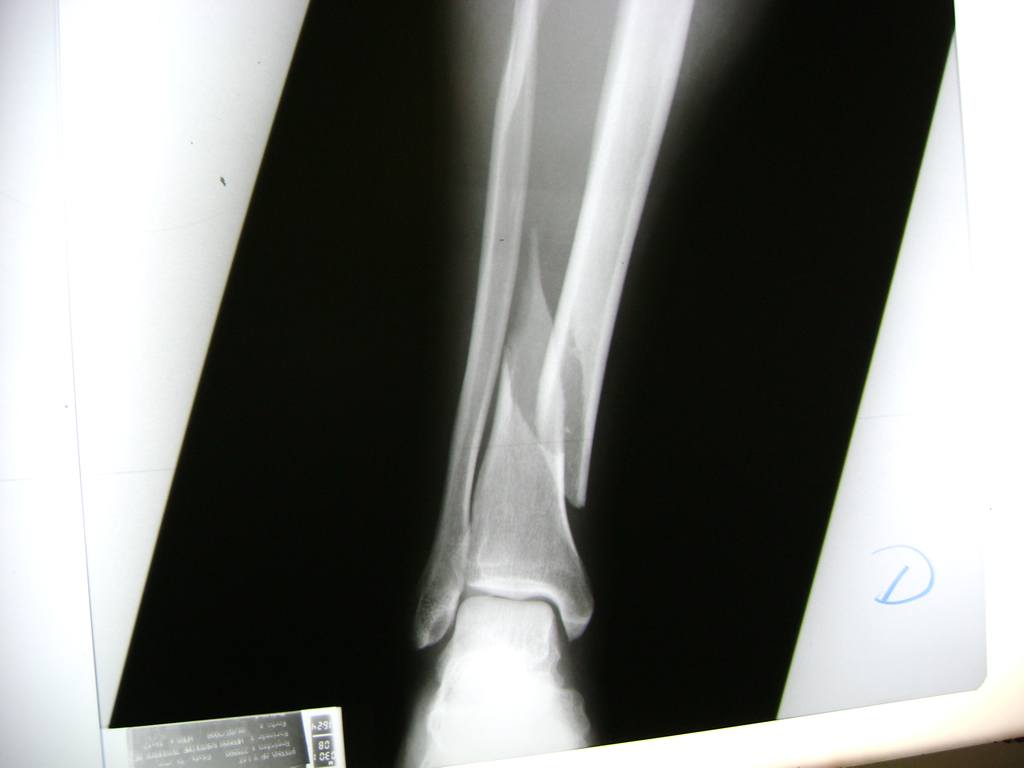

La mayor parte de las roturas implican a la parte proximal del hueso (parte del hueso próximo a la rodilla) o a la parte distal (parte del hueso cerca del tobillo).

Debido a la fina cobertura de piel que recubre la tibia y el peroné, las fracturas generalmente son abiertas, es decir, el hueso roto rasga la piel, atravesándola. Las fracturas de tibia y peroné generalmente se producen por un fuerte impacto o torsión.